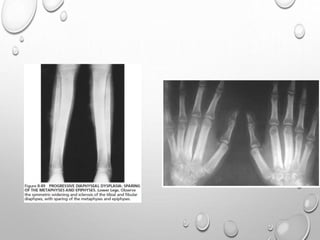

• Epiphyseal dysplasia – small

under ossified epiphyses

• Metaphyseal dysplasia – widened,

flared or irregular metaphyses

• Diaphyseal dysplasia – cortical

thickening or obliteration of marrow

space

Epiphyseal Dysplasia Metaphyseal Dysplasia